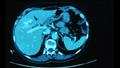

ومن أبرز المخاطر الصحية التي تنتج عن تناول هذا الطعام، الإصابة بسرطان الكبد، كما أن تحتوي تلك الأسماء التي لم يذكر نوعها، على الديدان المفلطحة الطفيلية، أو الديدان المثقوبة الحية التي تعيش بداخلها، وعادة ما تعيش تلك الديدان في الأسماء الموجودة بالمياه العذبة.

وغالبًا ما تصيب تلك الديدان القنوات الصفراوية، ويتطور الأمر إلى الإصابة بسرطان الكبد، ويؤدي إلى وفاة أكثر من 20 ألف شخص سنويًا، ومن بينهم والدي طبيب تايلندي يدعى " نارونج خونتيكيو"، الذي يحاول وعي الأشخاص وخفض عدد الأشخاص التي تتناول هذا الطبق.

وذكر جراح الكبد، أن والديه فارقوا الحياة نتيجة إصابتهم بسرطان الكبد، من الأمراض التي يطلق عليها القاتل الصامت، وذلك نظرًا لأنه أحد أقل معدلات البقاء على قيد الحياة بين أنواع السرطانات الأخرى، إذا لم يتم الكشف المبكر عنه وعلاجه.